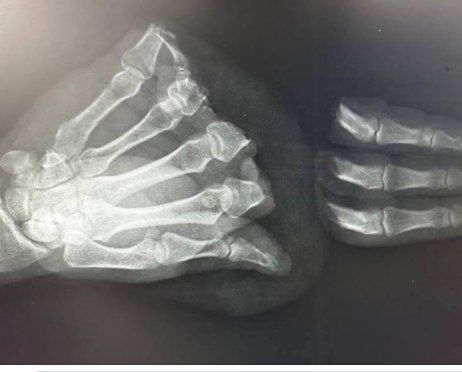

Жителю Москвы провели операцию по восстановлению трёх пальцев, которые он повредил циркулярной пилой во время выполнения домашних работ. Операция длилась около 13 часов. К сожалению, мизинец не удалось восстановить из-за особенностей травмы. После 10 дней в стационаре пациента выписали с рекомендациями по дальнейшей реабилитации.